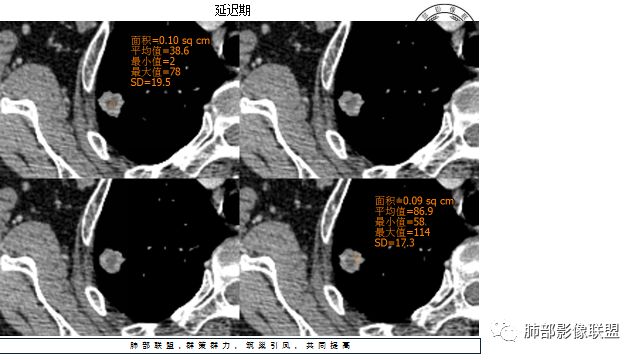

胸CT:右上肺结节,病灶位于胸膜下,边缘可见平直 u型征 软毛刺 晕,增强可见延迟强化,病灶中心低密度区。

4.增强扫描成明显环形强化,中央液化坏死,内壁清楚且较为规整。